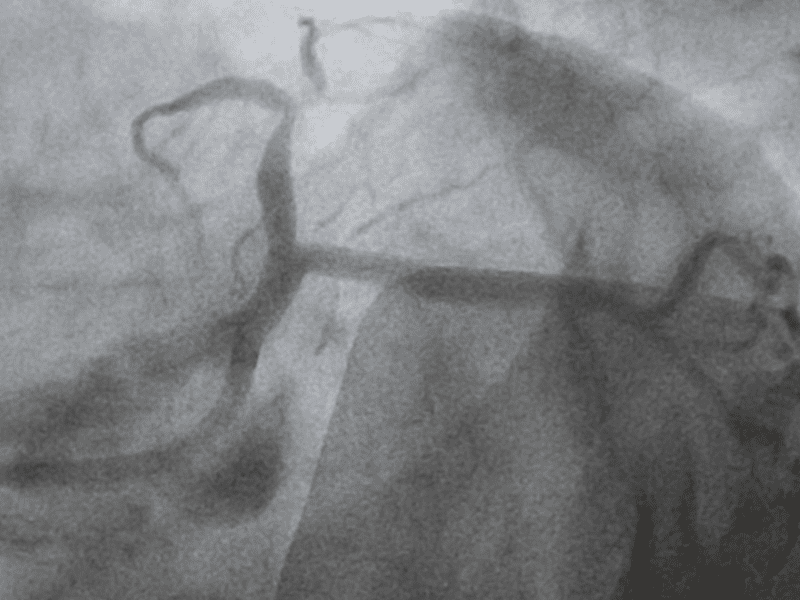

- Angioplastica: Un intervento minimamente invasivo per dilatare le arterie ristrette, ripristinando il flusso sanguigno.